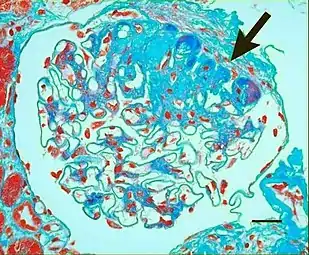

In benign nephrosclerosis, the changes occurring are gradual and progressive, however, there can be sufficient kidney reserve capacity to maintain adequate kidney function for many years.[9] The large renal arteries exhibit intimal thickening, medial hypertrophy, duplication of the elastic layer. The changes in small arterioles include hyaline arteriolosclerosis (deposition of hyaline, collagenous material), which causes glomerular collapse (wrinkling and thickening of capillary basement membranes and collapse of capillary lumen) and solidification (glomeruli exhibit sclerosis and increase in mesangial matrix). The degree of scarring correlates with the degree of glomerular filtration deficit.

Light micrograph showing hypertensive glomerular lesion of hypertensive nephropathy: global glomerular collapse and filling of Bowman’s space with a lightly staining collagenous material.

Light micrograph of glomerulus showing secondary segmental sclerosis of hypertensive nephropathy.